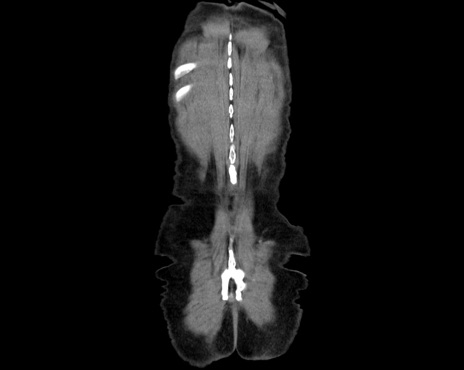

横断像